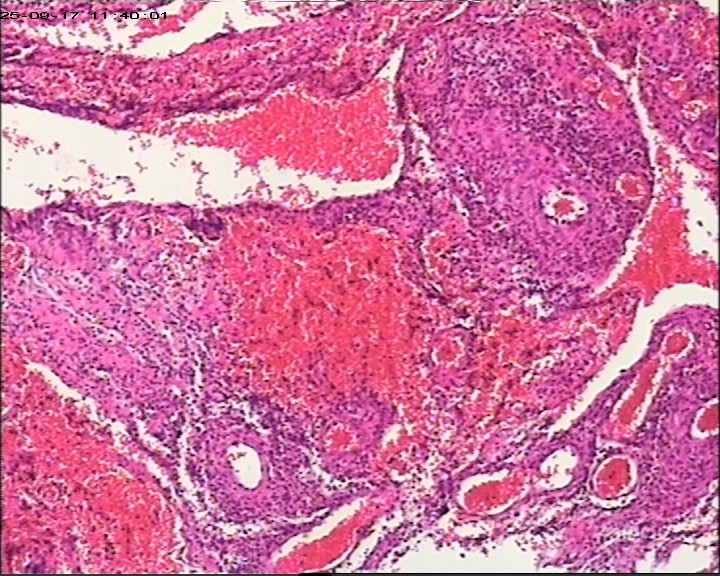

臀部组织,请帮忙看看,谢谢

性别

男

年龄

20岁

临床诊断

一般病史

藏毛窦或囊肿切开术

标本名称

臀部

灰白灰黄碎组织一堆,大小为6.5*4*1cm。

描述诊断炎性病变